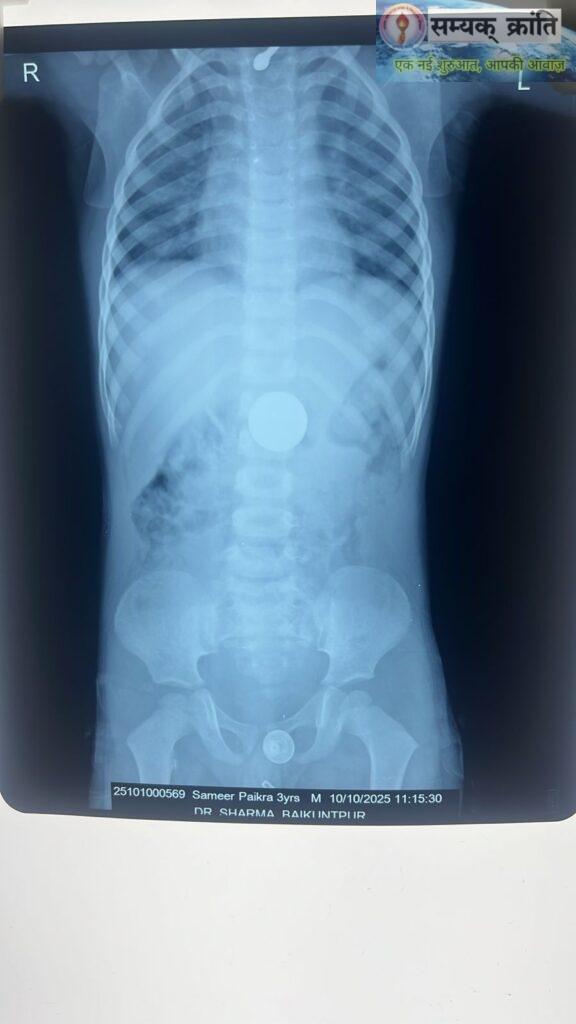

बैकुंठपुर (कोरिया)। ग्राम सक्ति पारा निवासी 3 वर्षीय बालक समीर पैकरा खेलते-खेलते ₹10 का सिक्का निगल गया, जिससे परिजनों में बच्चों को लेकर भय व्याप्त हो गया था। परिजन पिछले एक सप्ताह से परेशान थे और जब कोई उपाय कारगर नहीं हुआ, तब वे दिनांक 10 अक्टूबर को बैकुंठपुर स्थित शर्मा अस्पताल पहुंचे।

अस्पताल में डॉ. संकल्प शर्मा ने बच्चे का एक्स-रे कराया, जिसमें स्पष्ट हुआ कि सिक्का बच्चे की खाने की थैली तक पहुंच गया है। यह स्थिति अत्यंत जोखिमभरी थी। डॉक्टर संकल्प शर्मा ने तुरंत निर्णय लेते हुए बच्चे को एनेस्थीसिया देकर एंडोस्कोपी के माध्यम से मात्र 10 मिनट में ही सिक्का सफलतापूर्वक बाहर निकाल लिया।